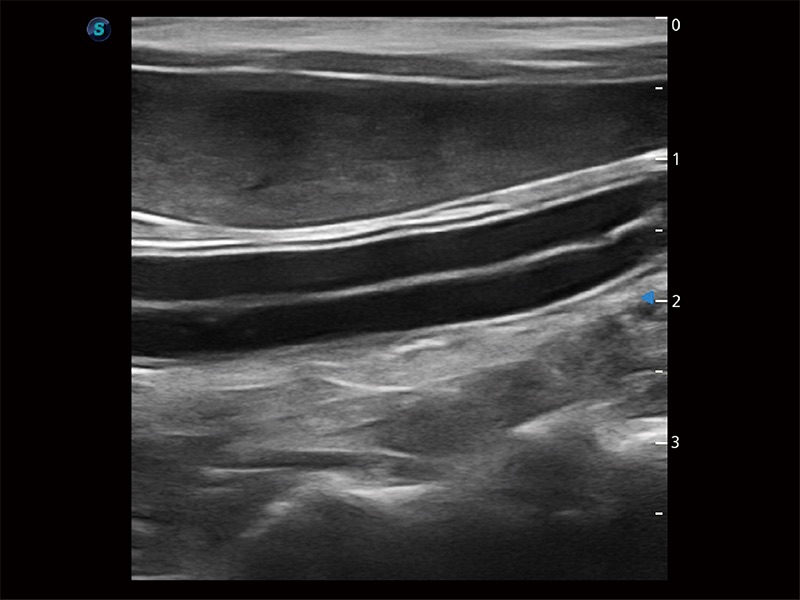

高性能和先进的临床应用工具可以为动物医生提供临床信心。ProPet 80 搭载了先进的腹部和浅表应用工具,帮助医生在日常临床实践中发挥前所未有的作用。

极大提升超低速微细血流的检出能力,同时更精准地滤除软组织和超声信号,为兽用医生提供以往无法通过常规血流获得的疾病诊断信息。

操作简便,无需高频度外力作用即可真实反映组织的形变,快速评估肿瘤良恶性。